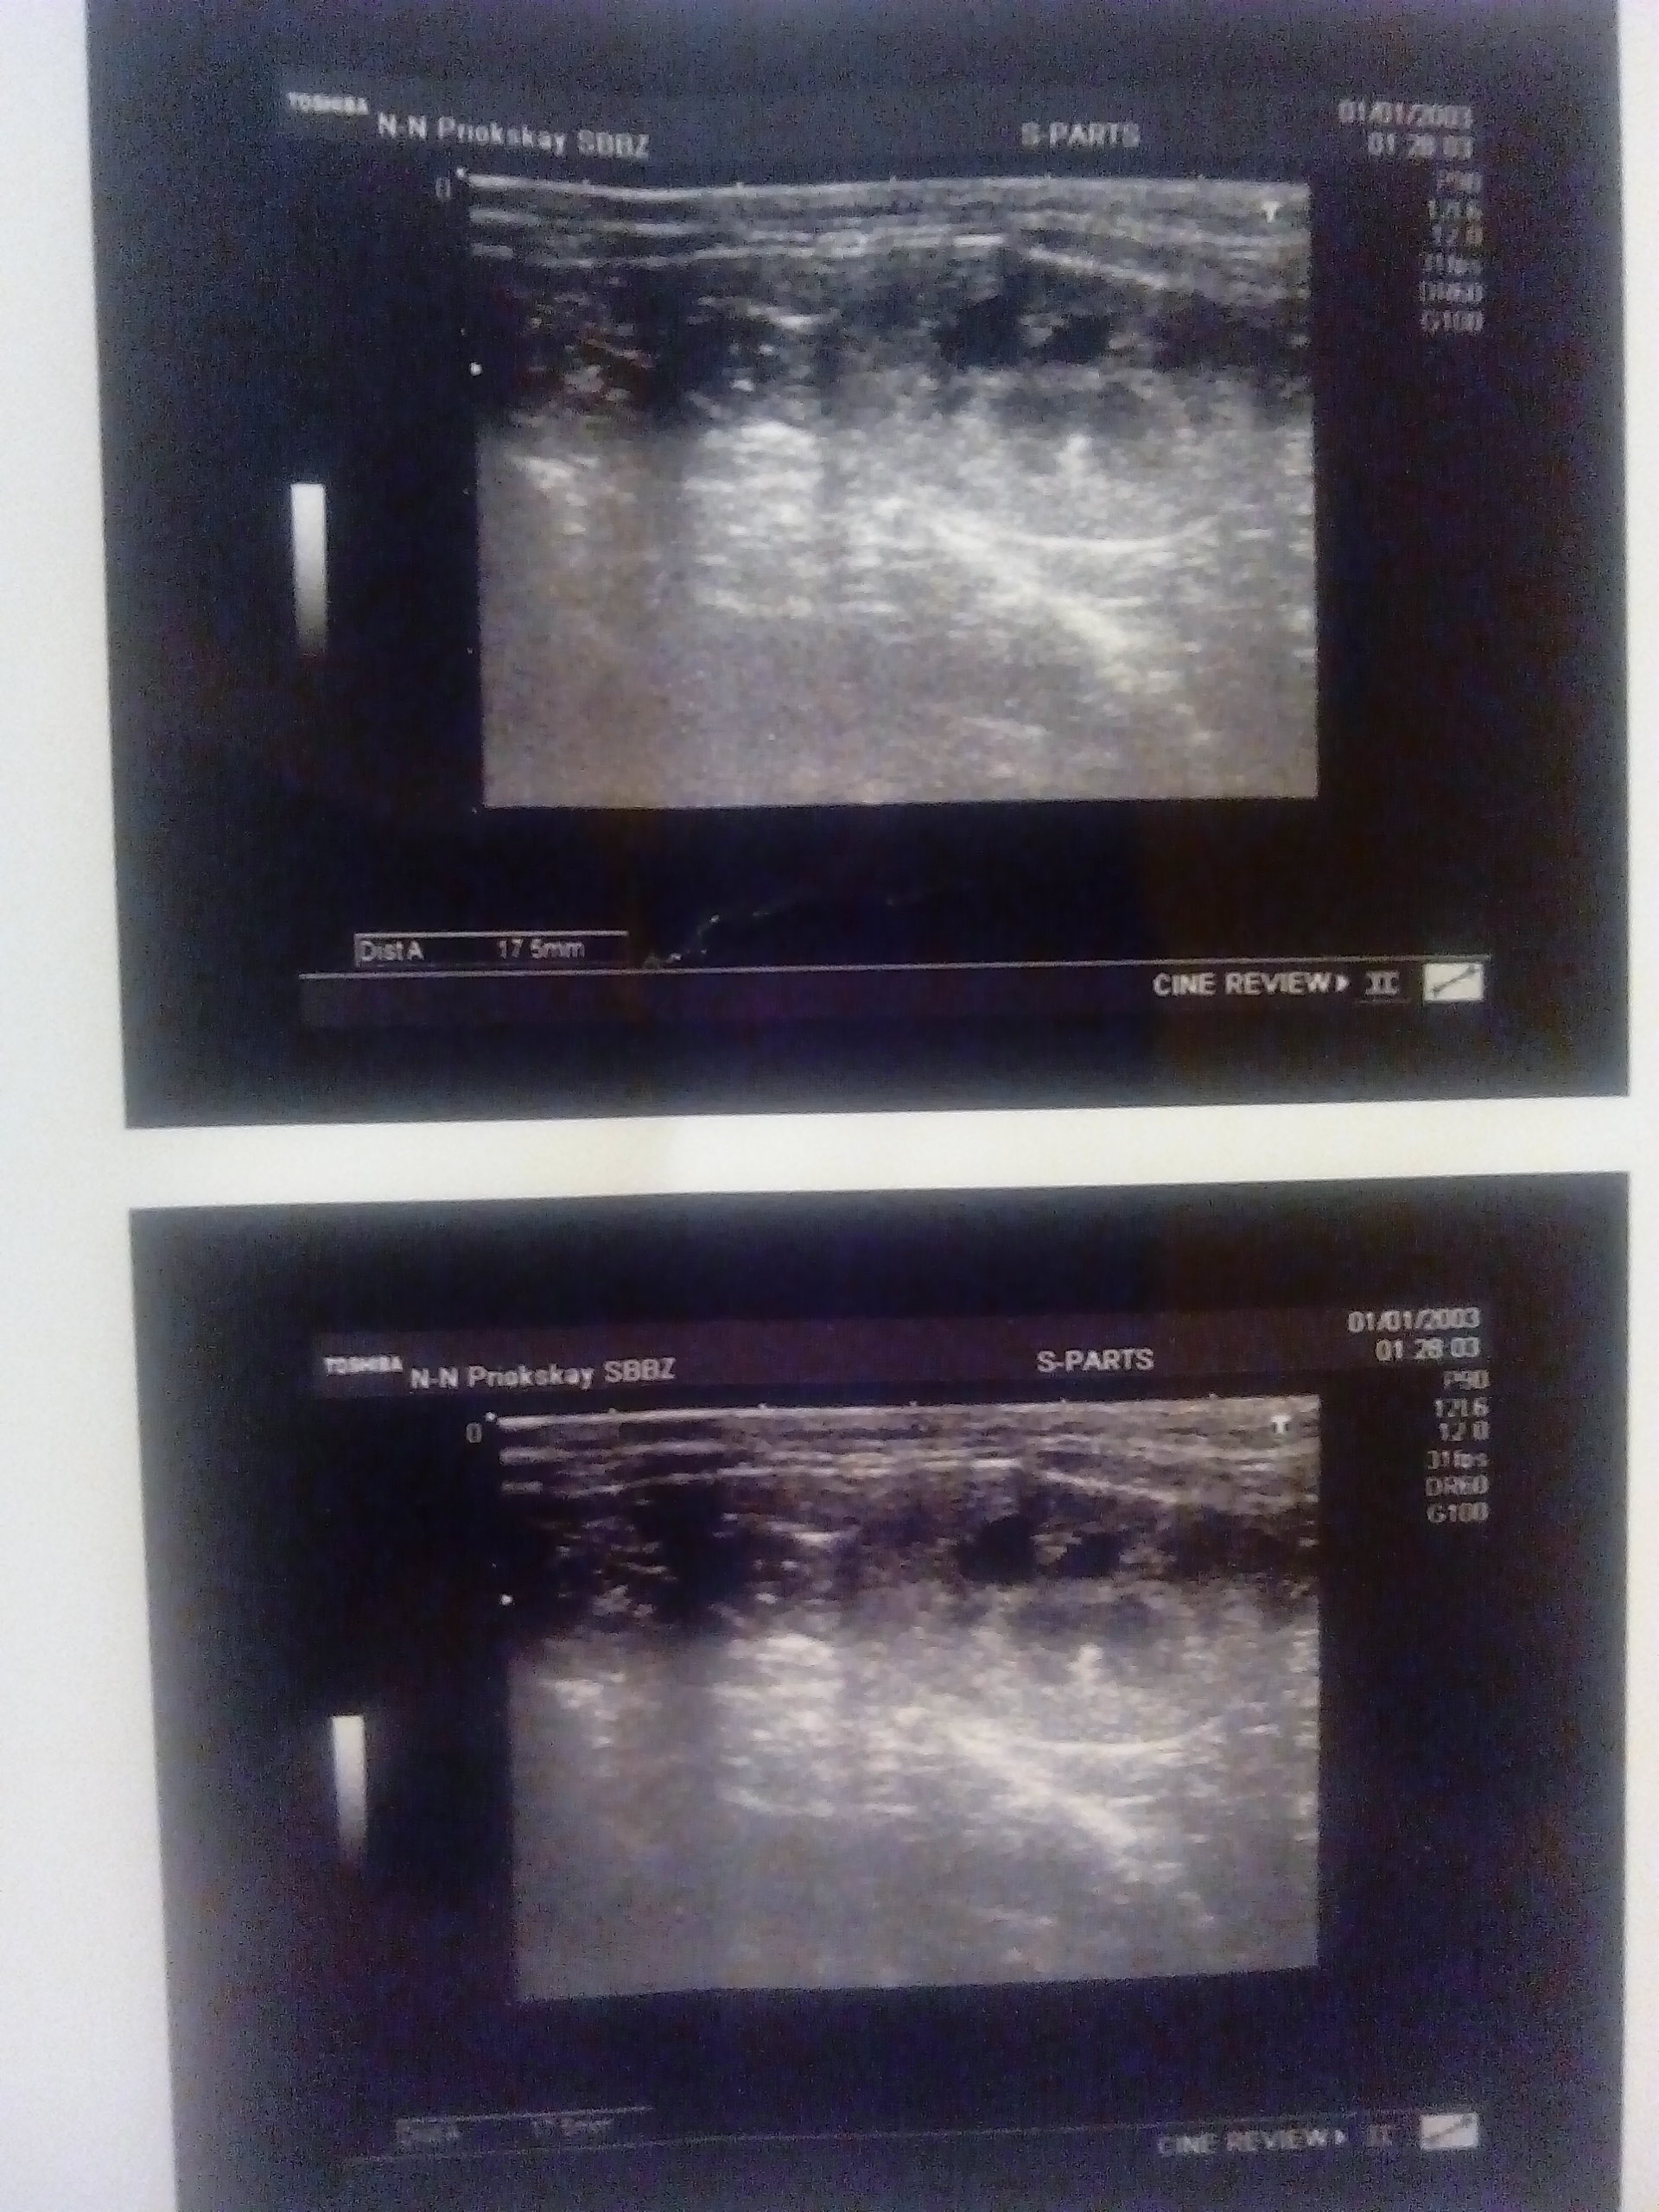

С Мусей во вторник 5.06.2018 ездили на узи в приокскую клинику.

В мочевом много взвеси, одна почка нормальная, вторая почка с расширенной лоханкой (пиелонефрит)(((.

Печень врач смотрела, ничего подозрительного не нашла.

Узи специалист мне понравилась, это первый врач узи, который засыпал меня вопросами про анализы про самочувствие, я была в радостном шоке тк видно, что этот врач не как робот делает узи и пишет заключение, а ещё и собирает анамнез для общей картины + делает узи. Всё показывает и рассказывает.

Я снова ехала домой в слезах(, хотя, по сути всё что узнала и так знала. Завтра отправлю результат врачу, которая нас направила на узи, болезнь не излечима, но надо подобрать правильную терапию, чтобы стабилизировать ситуацию + скорее всего Муся снова сядет на лечебную диету(это пока, только мои рассуждения последнее слово за врачом). Очень надеюсь, что этот врач нас "не бросит" и поможет.